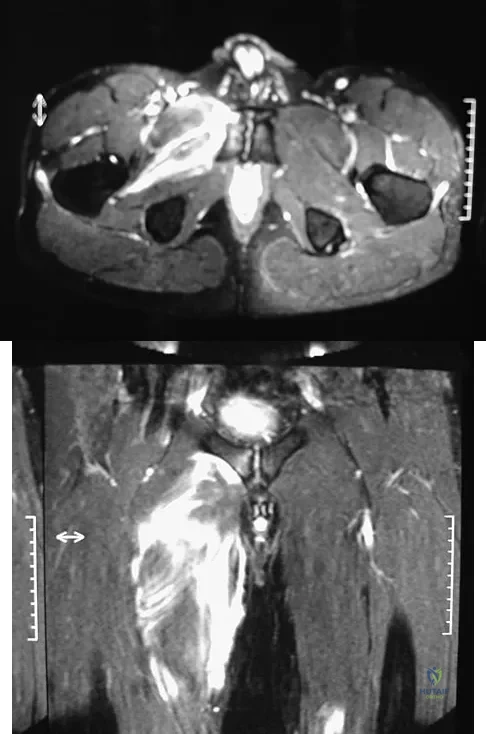

Figures 28a and 28b show the sagittal and axial lumbar MRI scans of a 72-year-old man who reports dull aching back pain that spreads to his legs, calves, and buttocks. He has had the pain for several years and it is precipitated by standing and walking and relieved by sitting. His symptoms have been worsening over the past year and he notes that he is leaning forward while walking to help relieve his symptoms. He has had no treatment to date. What is his prognosis if he chooses to pursue nonsurgical management for this condition?

The patient has lumbar spinal stenosis and the MRI scans reveal the pathology at L4-5, which is secondary to posterior disk bulging and hypertrophy and infolding of the ligamentum flavum, as well as degenerative facet arthrosis. The degree of spinal stenosis is moderate and his symptoms are positional in nature. Tadokoro and associates reported on a prospective study of 89 patients older than 70 years of age who underwent nonsurgical management for lumbar spinal stenosis. They found the prognosis to be relatively good with patients scoring at "excellent" or "good" for activities of daily living at final follow-up. However, they did note that patients with a complete block on myelography did not respond favorably to nonsurgical management. Amundsen and associates reported on a 10-year prospective study comparing surgical care to nonsurgical management. They concluded that, while the long-term results largely favored surgical treatment, more than half of the nonsurgically managed patients had a satisfactory outcome. They also concluded that a delay of surgery for some months did not worsen the prognosis. Therefore, their recommendation was for an initial primarily nonsurgical approach. Amundsen T, Weber H, Nordal HJ, et al: Lumbar spinal stenosis: Conservative or surgical management? A prospective 10-year study. Spine 2000;25:1424-1435. Hilibrand AS, Rand N: Degenerative lumbar stenosis: Diagnosis and management. J Am Acad Orthop Surg 1999;7:239-249.